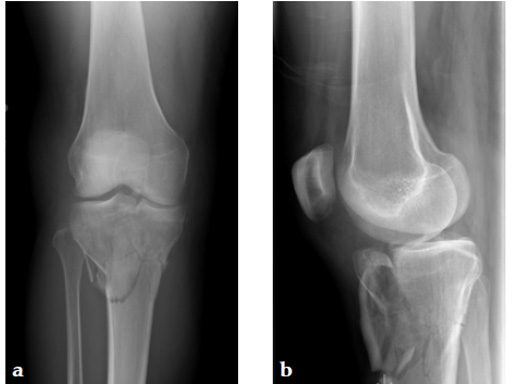

Staged management with initial rodding of femur and placement of spanning knee external fixator with closed manipulative reduction of tibial plateau (Fig 3).